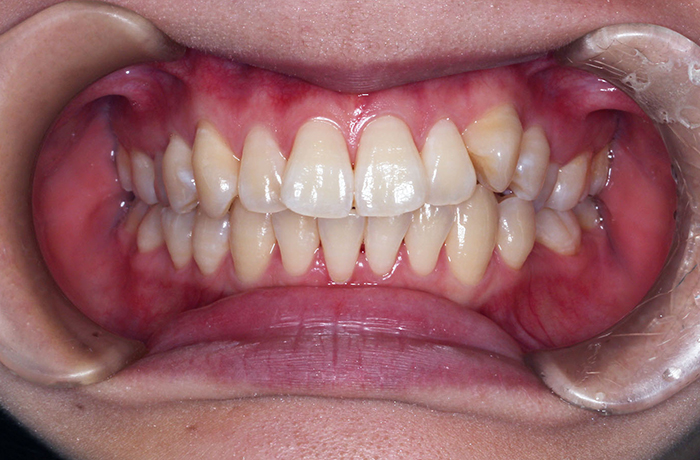

A様

治療前

before

年齢 31歳

性別 女性

治療名称 マウスピース型カスタムメイド矯正歯科装置(インビザライン)・コンプリヘンシブパッケージ(難症例)

総額治療費用 935,000円(税込10%) 金額備考 精密検査料・診断料 33,000円(税込10%)

治療期間 3年4か月 通院頻度など 1か月ごと(途中から3~4か月ごと)

マウスピースの装着時にホワイトニングを兼用

ホームホワイトニング 両顎 30,800円(税込10%)

患者の症状 叢生、正中のずれ、上顎左右側切歯の口蓋側転位(交叉咬合)

治療方法 非抜歯で、マウスピース型カスタムメイド矯正歯科装置(インビザライン)による矯正

歯列弓を拡大することで非抜歯を可能にしました。

治療結果 側切歯の交叉咬合は解消、上下正中のずれも改善し咬み合わせが良くなりました。

※治療結果は患者様によって個人差があります。

リスク/副作用 1日22時間以上、装置の装着時間が必要です。